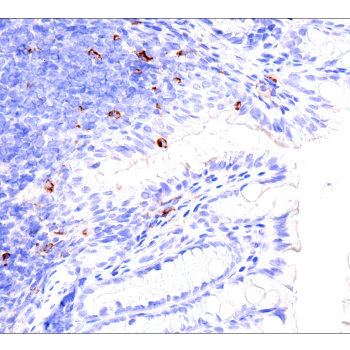

使用 PD-L2 (D7U8C™) XP® Rabbit mAb 对

石蜡包埋的人纵隔大 B 细胞淋巴瘤进行免疫组织化学分析。

使用 ICOS (D1K2T™) Rabbit mAb 对石蜡包埋的

人结肠癌细胞进行免疫组织化学分析。